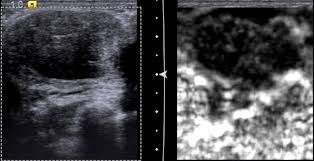

Patient With Breast Cancer And Bone Metastasis A Ct Scans At Baseline Download Scientific Diagram from www.researchgate.net The specialized cone beam breast ct (cbbct) scanner, developed by boone and colleagues, uses the same amount of radiation as a conventional mammogram. One example is a combined pet and ct scan (known as pet/ct), available in some centers. This is an excellent way to take a needle biopsy for inflammatory breast cancer because imaging can show the best place to take the biopsy. Right now, ct scans are not used routinely to evaluate the breast. All a ct scan will show is something different, for my wife they found something different in her lung and assumed it was lung cancer, turns out if was just some odd form of webbing/scar tissue and it was containing quite a lot of infection. A sentinel lymph node biopsy may first be performed to determine whether cancer has spread to the lymph glands under the arm. Mammograms take advantage of the fact that most of the female breast is fat tissue, so it's relatively transparent to the low doses of radiation used in mammography. It's an effective imaging test for finding cancer and learning its stage.

Knowing the stage helps your doctor decide which treatment you need. So far, researchers at the university have. Doctors often use this is for cancer staging. Mammography is currently the preferred examination for breast cancer screening; During a ct scan, you will be exposed to a small amount of radiation. The area covered in the scanning can be determined. The test has only a limited ability to detect small tumors. The cancer's stage describes the location of cancer, if it spread and if it's changing the function of your organs. A breast pet scan is often very specific and sensitive and is approved for patients. One example is a combined pet and ct scan (known as pet/ct), available in some centers. The specialized cone beam breast ct (cbbct) scanner, developed by boone and colleagues, uses the same amount of radiation as a conventional mammogram. Ct scans can show a tumor's shape, size, and location. The contrast helps to show up areas of increased vascularity and so it does help show up tumours as they have a rich blood supply.

Doctors often use ct scans to help them guide a needle to remove a small piece of tissue. Some fear that the ionizing radiation emitted from ct scans can harm dna and cause tumors. A sentinel lymph node biopsy may first be performed to determine whether cancer has spread to the lymph glands under the arm. When a breast cancer has been diagnosed, some people have a ct scan of their chest and tummy (abdomen) to stage the breast cancer. This helps determine whether or not the cancer can be removed with mastectomy. Ct scans are inaccurate for treatment monitoring after cancer treatment, a ct scan is unable to determine whether masses leftover are cancerous: This can allow for examination of neighboring organs and structures like lymph nodes to check for any signs of disease. This is an excellent way to take a needle biopsy for inflammatory breast cancer because imaging can show the best place to take the biopsy. In some cases, physicians use all three imaging techniques. Bone scans, positron emission tomography (pet), and computed tomography (ct) all continue to be employed alone or in combination for the detection of breast cancers suspected to have spread. It's an effective imaging test for finding cancer and learning its stage. How do ct scans work? The contrast helps to show up areas of increased vascularity and so it does help show up tumours as they have a rich blood supply.

The benefits of having a ct scan usually outweigh the risks. If you have a large breast cancer, your doctor may order a ct scan to assess whether or not the cancer has moved into the chest wall. Doctors can combine pet scans with ct scans. By comparing ct scans done over time, doctors can see how a tumor is responding to treatment or find out if the cancer has come back after treatment. Sandy,i asked my onc.he says ct's can pick up breast cancer depending part on location.i guess it's like real estate,location,location,location,lol.but seriously theradiologist who read my lung ct in november wrote in his report specifically there was no evidence of breast cancer.i guess due to them watching a lymph gland for 2 years on my rt breast.it was fine in mammogram in october so i am now back to yearly,thank god,andib Then, this evening, after talking to mum about the scan appointment, i looked up great cancer and read about inflammatory breast cancer and that sure does fit the bill, perfectly. All a ct scan will show is something different, for my wife they found something different in her lung and assumed it was lung cancer, turns out if was just some odd form of webbing/scar tissue and it was containing quite a lot of infection. One example is a combined pet and ct scan (known as pet/ct), available in some centers. Bone scans, positron emission tomography (pet), and computed tomography (ct) all continue to be employed alone or in combination for the detection of breast cancers suspected to have spread. Can a ct scan pick up breast cancer. After detecting the location of the tumor, the area will be biopsied for testing in the lab. Ct scans can show a tumor's shape, size, and location. This is an excellent way to take a needle biopsy for inflammatory breast cancer because imaging can show the best place to take the biopsy.